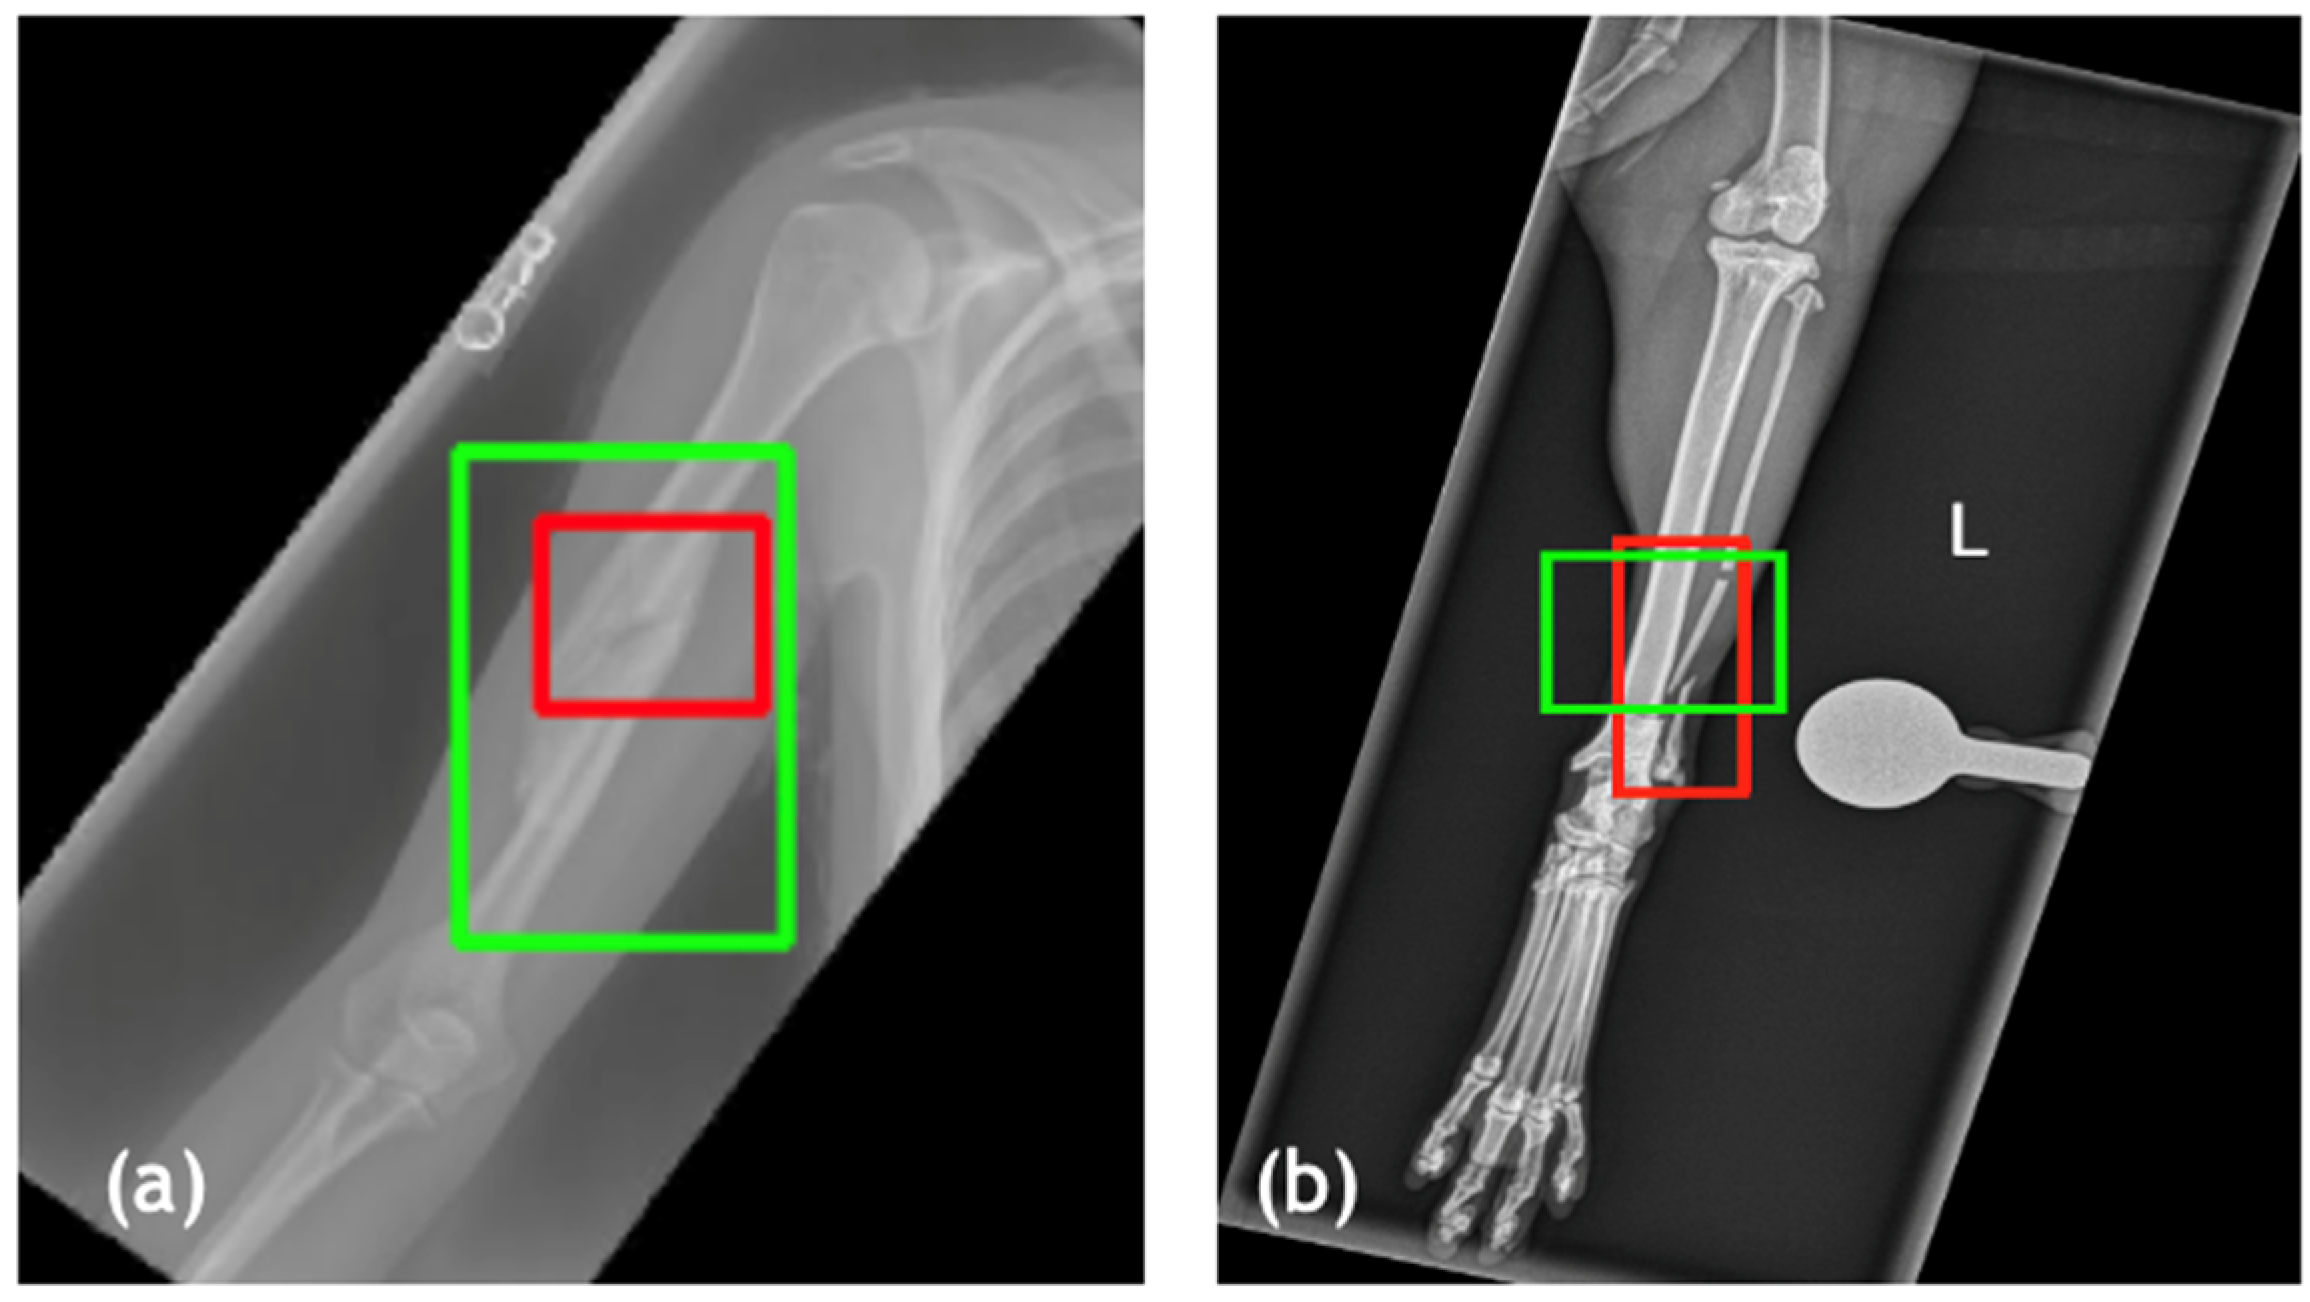

Exemplars model predictions with ground truth annotations (red boxes) and predicted fracture regions (green boxes) are presented in Figure 2. In hospital-derived training images (example in Figure 2a), the model demonstrated tight bounding box alignment with expert annotations, capturing cortical disruptions and fracture lines with high spatial precision. Literature-derived training images (example in Figure 2b) exhibited slightly lower overlap, likely due to variability in image resolution and positioning. In contrast, the test set images (example in Figure 2c) produced the most consistent and accurate predictions, reflecting the benefits of standardized imaging protocols. However, the model exhibited a degree of over-prediction, with the detected fracture regions extending slightly beyond the annotated ground truth.

Figure 2. Visual validation of fracture detection in equine datasets for dorsopalmar (DP) projections. Predicted bounding boxes (green) are compared with ground truth annotations (red). (a) Hospital-acquired training image with high IoU (0.73) and precise alignment. (b) Literature-derived training image with high overlap (IoU = 0.74), reflecting variability in positioning [2]. (c) Test set image with high localization accuracy (IoU = 0.81), demonstrating effect of high-quality, standardized imaging protocols.